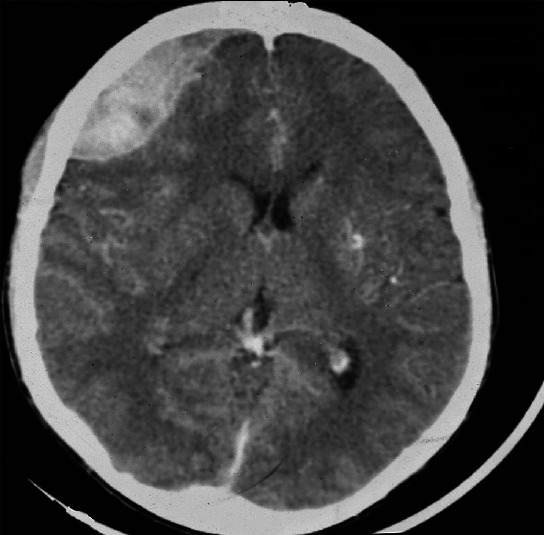

非外伤性自发性硬膜外血肿是镰状细胞病中一种罕见且常未被提及的并发症。它常与颅骨梗死有关。我们报告一位十八岁的镰状细胞性贫血的男孩,他在血管闭塞危机期间出现了持续性头痛。脑部电脑断层扫描(CT)显示右侧额叶硬膜外血肿(EDH)压迫脑部。未发现其他病因。右额叶开颅并清除血肿,患者恢复良好。本文还讨论了这种罕见疾病的可能病因。

Non traumatic spontaneous epidural Haematoma is a rare and often unmentioned complication of sickle cell disease. It is often associated with skull bone infarction. We report an eighteen year old boy with sickle cell anaemia who developed persistence headache during a vaso-occlusive crisis. Brain computed tomography (CT) revealed a right frontal epidural Haematoma (EDH) compressing on the brain. No other etiologic factor was identified. A right frontal craniotomy and evacuation of the Haematoma was performed and he made good recovery. The possible pathogeneses of this rare condition are discussed.